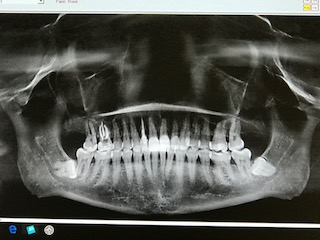

My “before” dental X-ray and possible Halloween mask. Too scary?